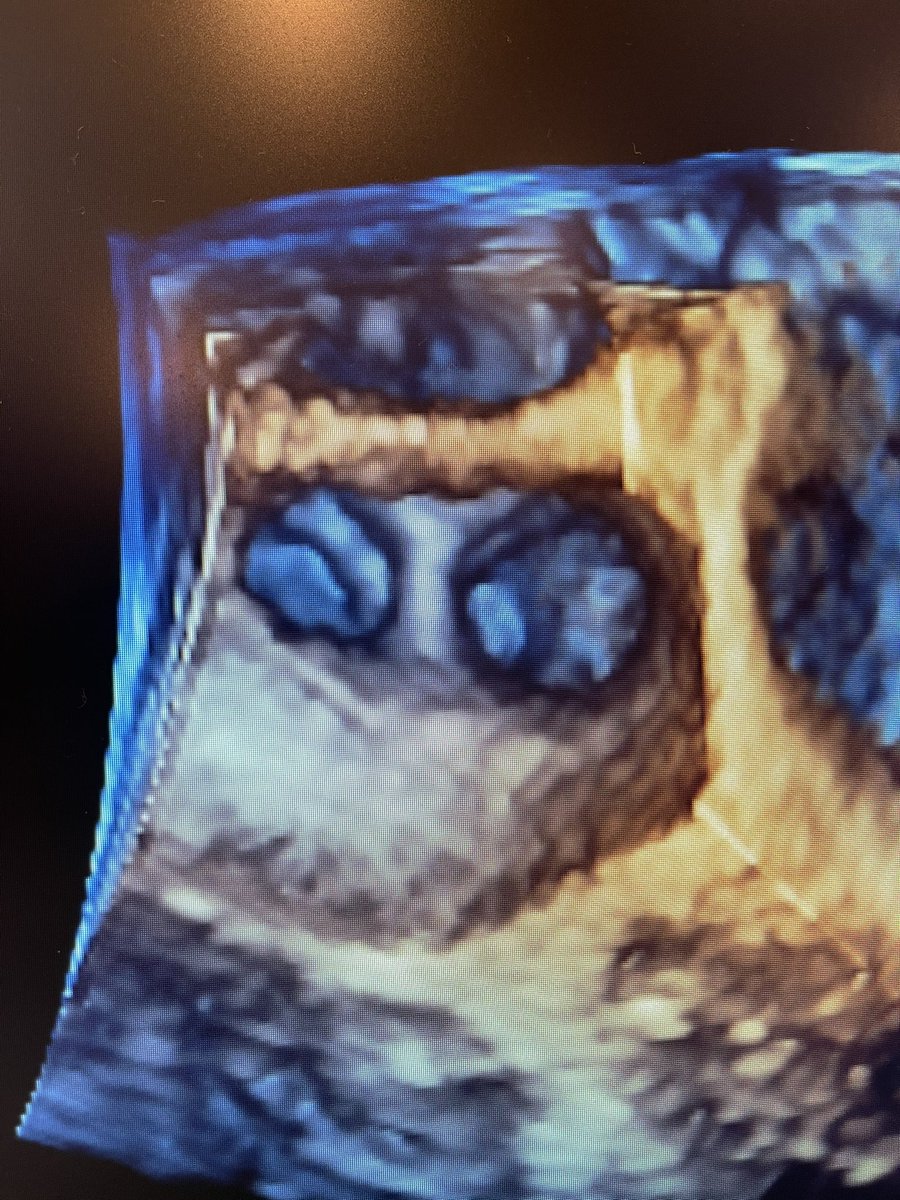

@AatishGarg_EP @VirtuaHealth @HeartVirtua @EPeeps_Bot @HeathHsalt Nice tracings! Nice case of isolated left atrial appendage in atrial fibrillation with exit block after Ostial isolation